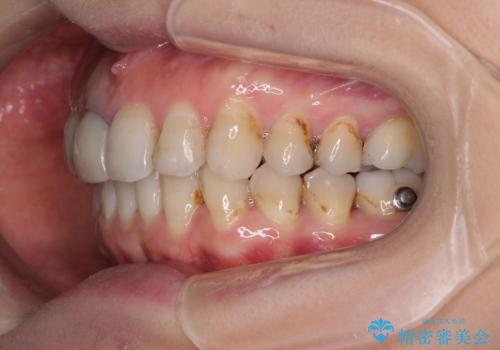

- 前歯の歯並びやむし歯治療の跡、奥歯の銀歯を気にして来院された患者様です。

インビザラインによる矯正治療の後に虫歯や銀歯をセラミックにて補綴することとしました。

前歯のむし歯治療の跡や奥歯の目立つ銀歯がなくなり、明るい口元になりました。